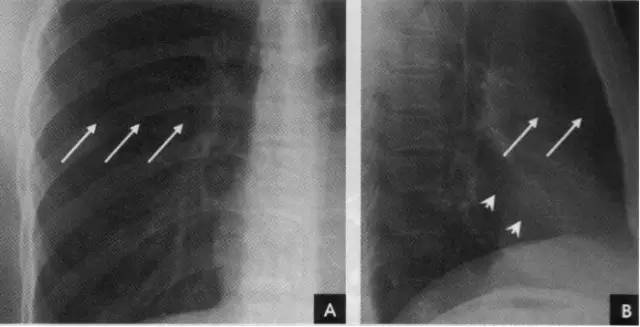

1、斜裂 一般在正位片上不能显示.在侧位片上表现为自后上斜向前下的线条状阴影:右德斜裂的后端起始于第4、5胸椎水平,斜向前下方走行,止于膈面距前缘2~3cm处,与膈顶部的水平面约成50°角;左侧斜裂后端起始点较右侧稍高,在第3~4后肋端水平,因而其倾斜度也较右饲稍大,前下端达肺的前下角处,与膈顶水平面约成60°角。叶间胸膜面通常略有弯曲,斜裂上半部稍斜向外,下半部稍斜向内,故在侧位片上可成s形。

2、横裂又称水平裂,约70%的人正、撼位胸片均可显影。在正位片上表现为右中肺野横行细线状阴影,从第6肋腋部水平自外向内延伸.并止于肺门外lcm处。可向上或向下倾斜10:左右或略成曲线;在侧位片上,横裂起白斜裂中部,向前呈水平方向走行达前胸壁。其位置的改变可作为判断肺体积变化的标志(如上图)。